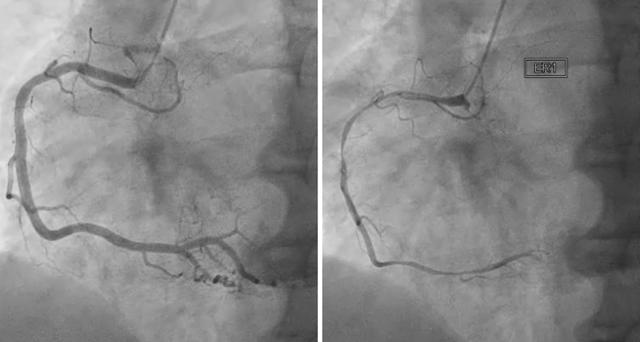

관상 동맥 질환

관상동맥 질환(CAD)은 심장에 혈액을 공급하는 혈관이 플라크가 쌓여 좁아지거나 막힐 때 발생합니다. CAD는 심장 근육으로 가는 혈류를 감소시켜 부정맥을 유발할 수 있으며, 이는 전기 시스템을 손상시키고 심장 리듬을 방해할 수 있습니다.